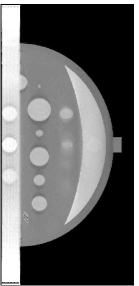

A breast phantom was designed to provide a basis for algorithm comparison. It consists of objects with different geometric shapes to allow for analytic computation of the projection data. The overall shape of the compressed breast of 50 mm thickness is modeled by a truncated ellipsoid. Attenuation coefficients at a photon energy of 30 keV [10] were used for phantom materials simulating the fibroglandular, tumour and muscle tissues, as well as microcalcifications in the breast. In Fig. 1, we display the phantom images within 2D planes specified by (a) mm, by (b) mm, (c) mm, and (d) mm, respectively. As shown in Fig. 1a, the crescent-shaped region, representing the fibroglandular tissue region of the breast, is attached to a rectangular slab of higher attenuation, simulating the pectoralis muscle. It can be observed in Fig. 1 that numerous test objects of different sizes and contrast levels are embedded in the phantom for simulating mass lesions and microcalcifications. In particular, a row of three ellipsoids is embedded in the pectoralis muscle (see Fig. 1(b)), with equal in-plane diameters but varying flatness, thus allowing one to evaluate whether shapes of equal in-plane profile, but different in-depth profiles, can be resolved. Furthermore, six spheres of different diameters, ranging from 5 mm to 15 mm, are equally distributed in the fatty area of the breast (see Fig. 1(c)). It can also be observed in Fig. 1(d) that three pairs of stacked spheres of identical diameter mm are embedded in the breast region with different spacings of , , and , respectively, for these pairs. Finally, two clusters of small spheres of diameters 0.3 mm and 0.15 mm are included to model microcalcifications.